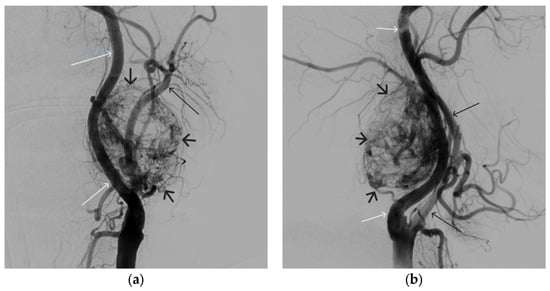

A 35-year-old male patient was admitted to the clinic with complaints of a cosmetic defect in the lower lip area. He has been ill since birth; 18 years ago he was diagnosed with AVM of the lower lip and microsurgical removal was performed. Over the past three years, the growth of formation has been noted. Angiography revealed a relapse of arteriovenous malformation with afferents from the left facial artery (Figure 3). In three years, he underwent several stages of treatment: endovascular embolization with gelatin sponge and embolization with pure ethanol, without effect. The patient underwent endovascular embolization of the AVM of the lower lip with 5 mL of non-adhesive composition ONYX18. Arteriovenous malformation was shut down totally (Figure 4, Figure 5 and Figure 6). The patient was directed to the next stage of surgical treatment—AVM removal by cosmetic surgeons (Figure 7). The mRs score at discharge was 1.

Figure 3. Digital subtraction angiography from the facial arteries: (a,b) straight and lateral projections on the left; (c,d) straight and lateral projections on the right (white arrows indicate catheters at the ostium of the facial arteries, black long arrows indicate filling of the lower lip AVM, black short arrow indicates the afferent AVM from the left facial artery). There is filling of the AVM from the afferent from the left facial artery.

Figure 6. Digital subtraction angiography from the right and left facial arteries: (a) direct projection; (b) lateral projection (white arrows indicate catheters at the ostium of the facial arteries, black arrows indicate embolizate cast). The absence of AVM contrast is noted.